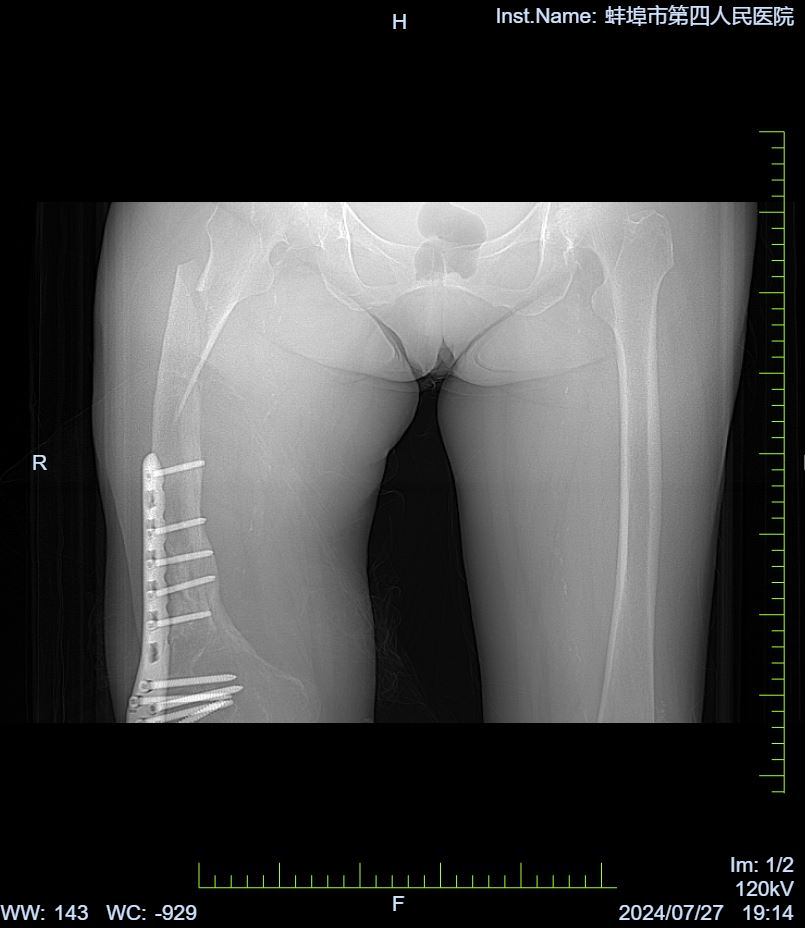

患者范奶奶今年70多岁了,因在家中不慎摔倒导致右侧大腿严重受伤,出现剧烈疼痛和外观畸形,活动受到限制,幸无皮肤破损及出血现象。伤后,范奶奶未出现头晕、头痛、心慌或气促等并发症,鉴于疼痛难忍,为求进一步治疗,她来到蚌埠市第四人民医院(市康复医院)骨科寻求帮助,经过门诊拍片后确诊为“右侧股骨干骨折”,随即安排入院治疗。

入院后,我院骨科团队迅速为范奶奶完善了相关检查,建议其卧床休息,同时采取抗炎止痛、患肢抬高牵引制动等综合治疗措施。值得注意的是,范奶奶右侧股骨有多次骨折病史,并接受过多次手术治疗。目前,她上次右侧股骨下段骨折的内固定装置尚未取出。针对这一复杂情况,我院骨科联合手术室(麻醉科)、护理部等多学科专家,对范奶奶的病情进行了全面而细致的评估与研讨,共同制定了周密的麻醉及手术方案。